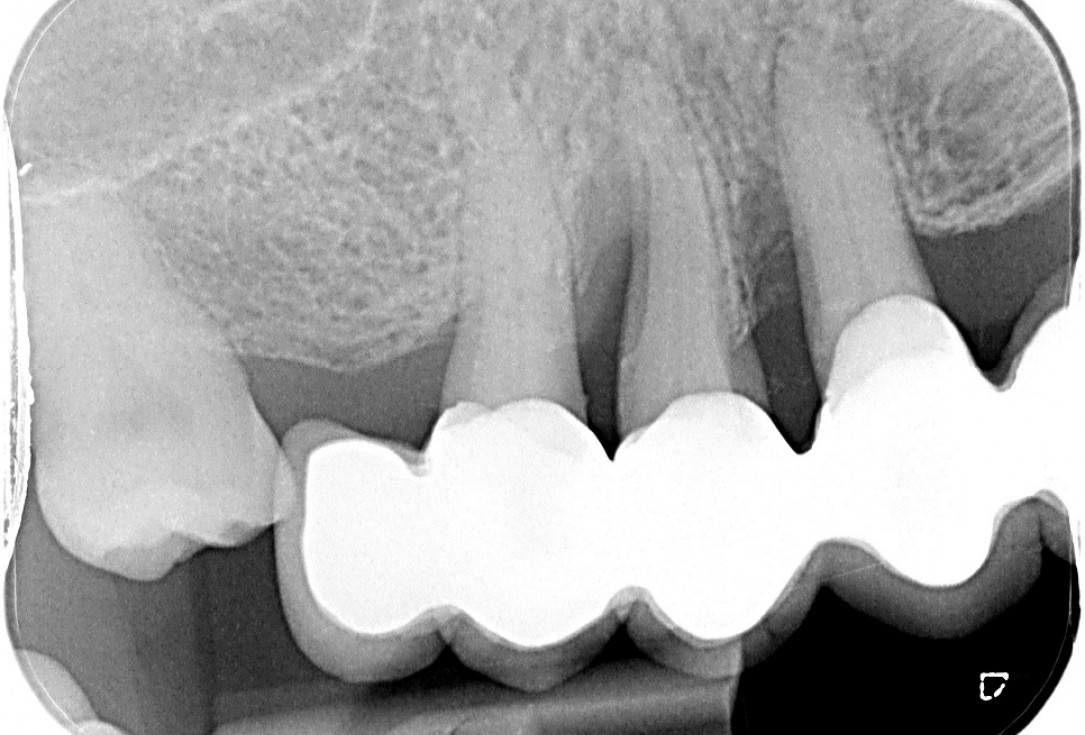

01/10 - Pre-operative OPG shows deep vertical intrabony defects on the distal aspects of teeth 13 and 14.GTR for the treatment of a deep three-dimensional intrabony defect using cerabone®, collprotect® membrane and Straumann® Emdogain® - Dr. T. Schwaar